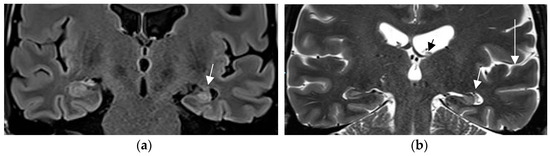

Anterior temporal encephaloceles are lesions defined as brain herniation through small—commonly antero-inferior—middle cranial fossa skull base defects in patients with temporal lobe epilepsy. These encephaloceles are recognized by scrutinizing the cortex of the anterior temporal lobe on coronal T2/Flair MR sequences. When identified and resected, anterior temporal encephaloceles had an excellent postsurgical outcome defined as ILAE Class 1 or 2 achieved in 85% of 20 patients [90]. The majority of these encephaloceles (20/37, 54%), however, had previously passed unrecognized on initial image interpretation even by experienced readers (Figure 10).

Figure 10.

Temporal meningoencephalocele depicted by herniation of the left temporal pole into a small anterior skull base defect with resultant CSF entrapment below the middle cranial fossa floor (a: coronal T2 w image 1.7 mm). A thin stalk of gliotic tissue connects to the left temporal pole (top arrow in coronal T2 (a) and arrow in sagittal FLAIR image 0.9 mm (b).

It is important to keep in mind that temporal meningo-encephaloceles have to be interpreted in the clinical context and in conjunction with EEG recordings, as this entity can also be present in subjects without epilepsy.

An additional entity that has increasingly attracted attention is nontumoral amygdala enlargement (Figure 11). Amygdala enlargement has been reported in 12% of patients with mesial temporal lobe epilepsy (MTLE) and was detected by volumetry and T2 relaxometry in patients without visible MRI abnormalities [91]. The etiology may be heterogenous: secondary and often reversible on MR in patients with adequate antiseizure medications response but may be termed “primary” based on amygdala dysplasia in those patients with an MR showing irreversible amygdala enlargement.

Figure 11.

Nontumoral right amygdala enlargement on a coronal T2 (1.7 mm arrow in (a)) and FLAIR sequence (0.9 mm) with signal elevation on the coronal FLAIR image (arrow in (b)) visually increased volume is confirmed to exceed 2nd standard deviation of normal value on volumetry (c).